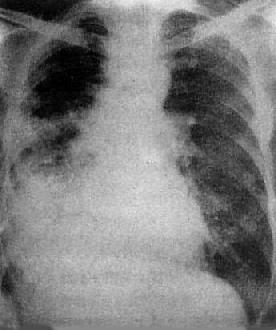

(2)液气胸:胸腔内液体与气体并存,为液气胸(hydropneumothorax)。可因胸腔积液并发支气管胸膜瘘、外伤、手术后以及胸腔穿剌时漏进气体而引起,也可先有气胸而后出现液体或气体与液体同时出现,明显的液气胸立位检查时可表现为横贯胸腔的液面,液面上方为空气及压缩的肺(图3-1-17)。气体较少时,则只见液面而不易看到气体。如有胸膜粘连,可形成多房性液气胸。

图3-1-17 液气胸

左肺萎陷,靠近纵隔,肺外有透明区,其中未见肺纹

理,下部致密,其上缘平直